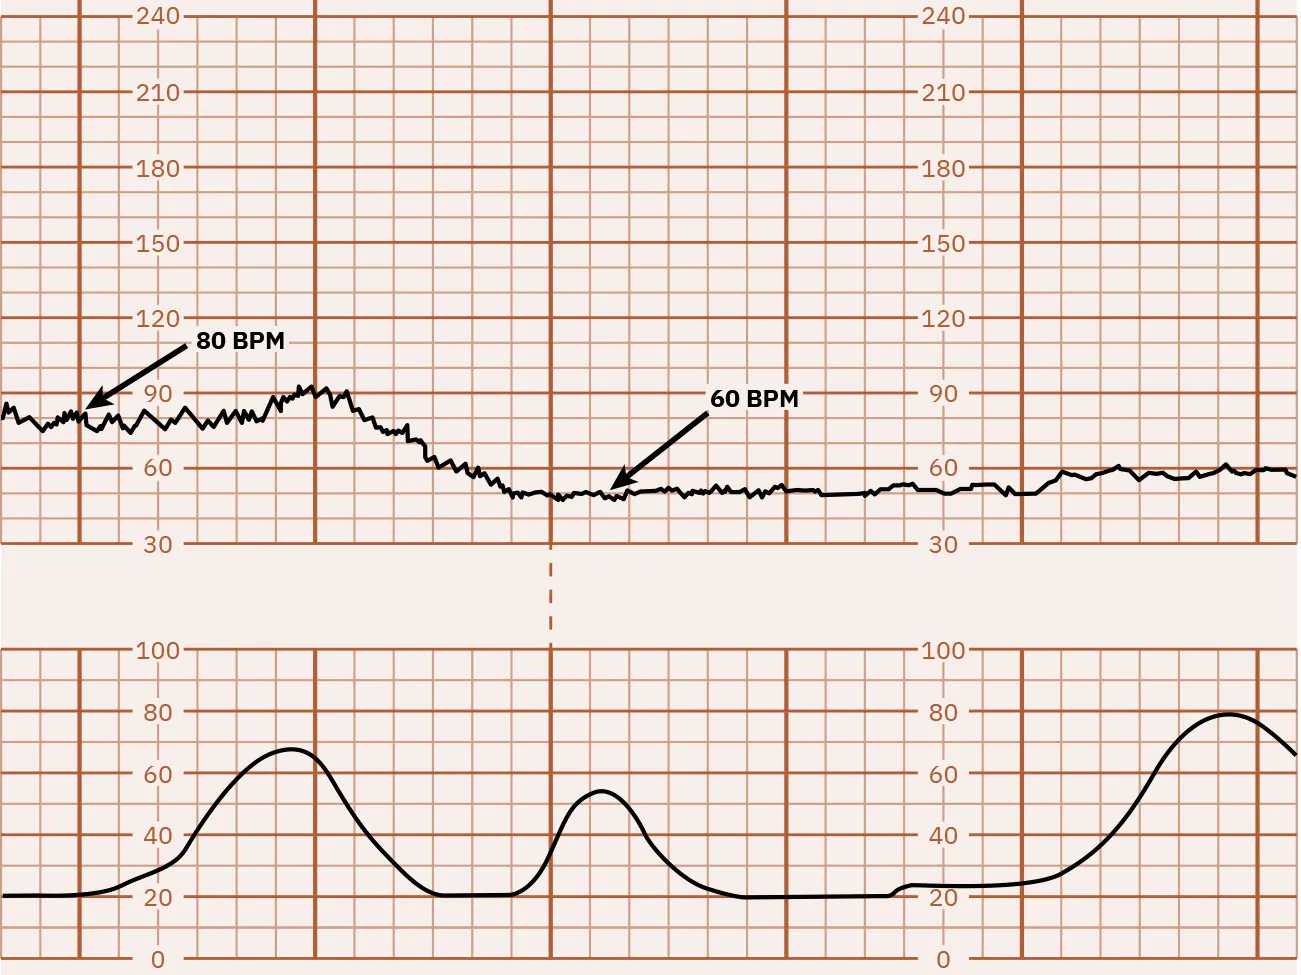

Bradycardia

Fetal bradycardia is defined as an FHR baseline less than 110 beats for 10 minutes. Figure 16.4 shows a monitor tracing that indicates FHR bradycardia. Bradycardia can be caused by multiple factors. The nurse must determine if the decrease in FHR is a benign episode of bradycardia or a pathologic prolonged deceleration (possibly lasting several minutes) that may need further intervention. Initial nursing actions for fetal bradycardia include repositioning the laboring person, administering intravenous (IV) fluid bolus, then notifying the health-care provider. See Table 16.2 for risk factors for fetal bradycardia.

Fetal heart rate reading indicating bradycardia.

Figure 16.4 Bradycardia This monitor tracing indicates bradycardia because the FHR is less than 110 bpm. (attribution: Copyright Rice University, OpenStax, under CC BY 4.0 license)